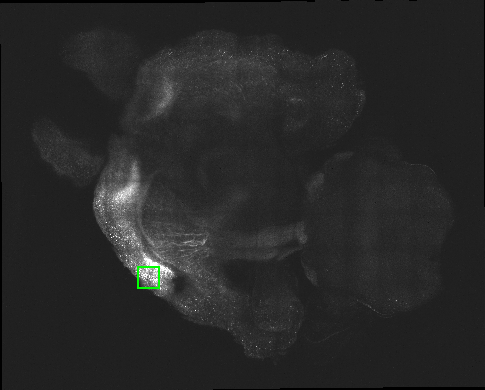

1.1 CLARITY

CLARITY avoids these problems by converting the brain into a translucent hydrogel-tissue hybrid. In the procedure, the brain is first perfused with hydrogel monomers and formaldehyde. When heated, the monomers and formaldehyde polymerize to form a molecular mesh which crosslinks amine groups of biological molecules. Since phospholipids lack amine groups, they do not crosslink with the mesh and can be eluted away with a strong detergent. The remaining hydrogel-brain hybrid is relatively translucent and permeable to fluorescent antibodies, making it amenable to labeling and interrogation by light-sheet microscopy. [2, 3] An axial slice through a CLARITY volume and magnified cutout are shown in Fig. 1.